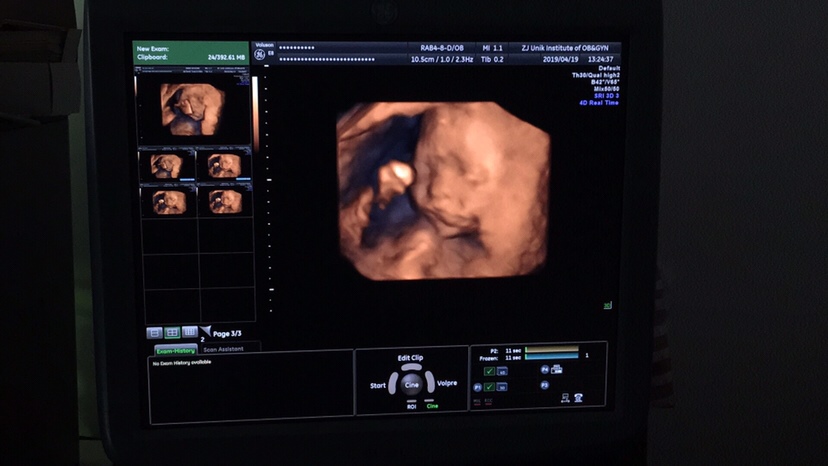

孕26周+1天

是的亲21-23周做四维

孕21周+1天

22周做的四维吗?